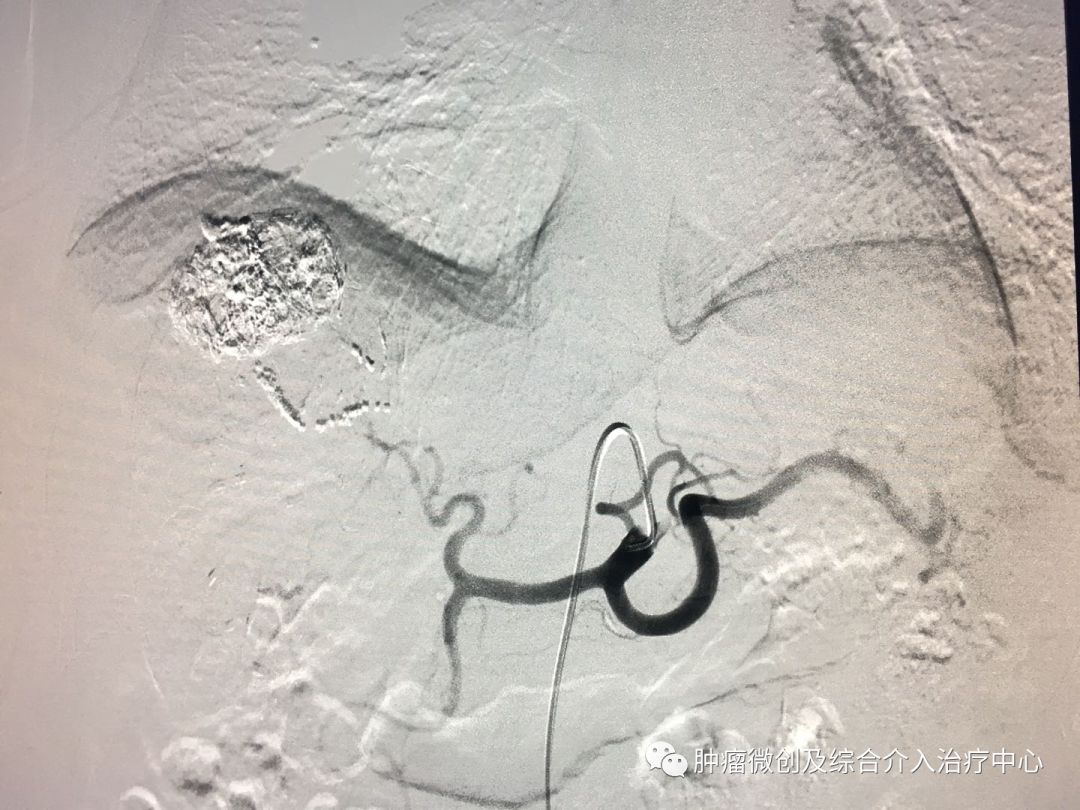

(肺动脉造影提示左肺动脉部分分支血管未显影,血栓形成,患者呼吸困难,胸闷、胸痛)

(经肺动脉导管溶栓治疗后,左肺动脉及其分支血管显影清晰,大部血栓溶解,患者呼吸困难症状改善,无胸闷及胸痛症状。)